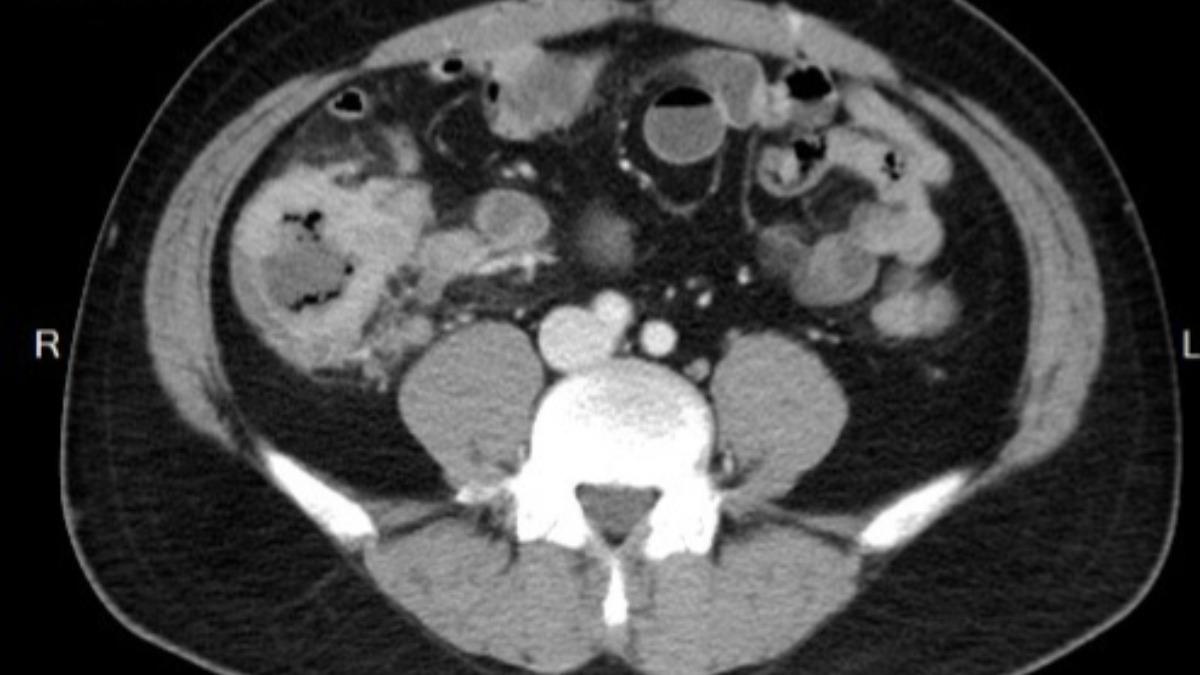

大腸癌初期症狀往往不明顯,千萬別因害怕檢查錯失治療良機!急診專科醫師貝琪梨日前分享令人惋惜的案例,一名48歲男子因一天連解3次血便前來求助,經檢查確診為大腸腺癌,最終手術切除右半側大腸。醫師透露,男子曾因覺得大腸鏡「戳進肛門」的感覺過於可怕,拒絕與母親一同檢查,若當初配合,也許一切都會不一樣。她沉痛呼籲,「預防勝於治療」,再忙也務必定期安排例行健檢。